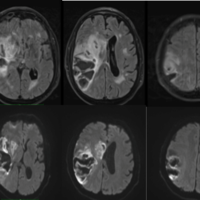

Vascular Cognitive Impairment (VCI) is a condition where the function of the brain is affected by diseases of the blood vessels, leading to problems with memory and thinking. It is the second most common cause of dementia, after Alzheimer’s disease.

We are a group of doctors, nurses, students, and research assistants who are looking to discover better ways to diagnose, prevent, and treat the conditions that cause vascular cognitive impairment, including treatment and prevention of stroke.